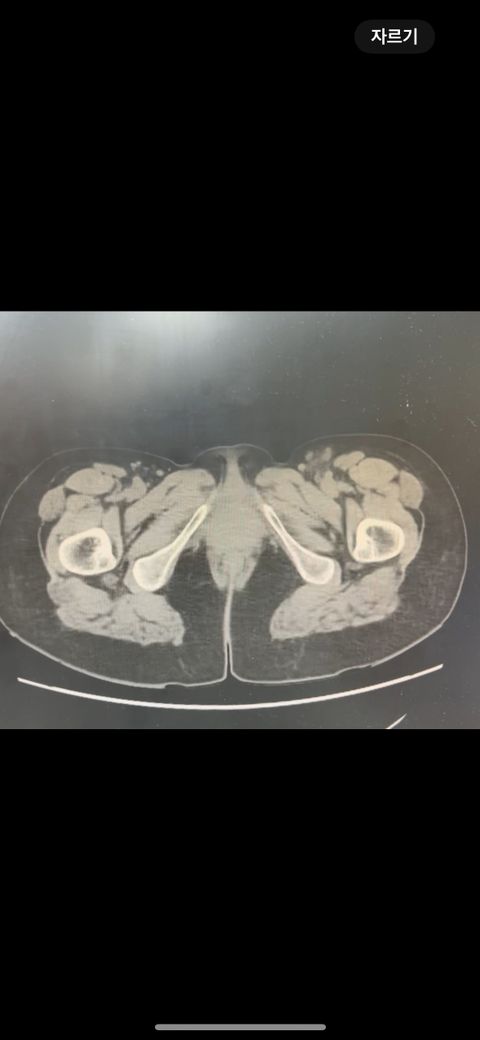

복부 ct 판독 부탁드립니다 (contrast)

결과는 3일 뒤 보긴 하는데 우선 영상만 있는 상태라 영상 캡쳐 한 거 대략적으로라도 확인해주실 수 있나요.. !!!!!!!!!!

• 4번 째 사진

*** 먼저 답변드리기에 앞서 상기 질문에 대한 답변은 굉장히 제한된 답변이고, 경우에 따라 틀린 답변이 될 수 있습니다. CT의 경우 단면을 연속적으로 봐야 의학적인 설명이 가능하기 때문에 일부 사진만으로는 해석이 어려울 수 있습니다.

위 사진에서는 비장비대의 가능성과 자궁쪽으로 혹이 일부 보이는 소견이 의심되나, 정확한 판독은 3일 뒤에 받아보시는 것이 도움이 될 수 있겠습니다.